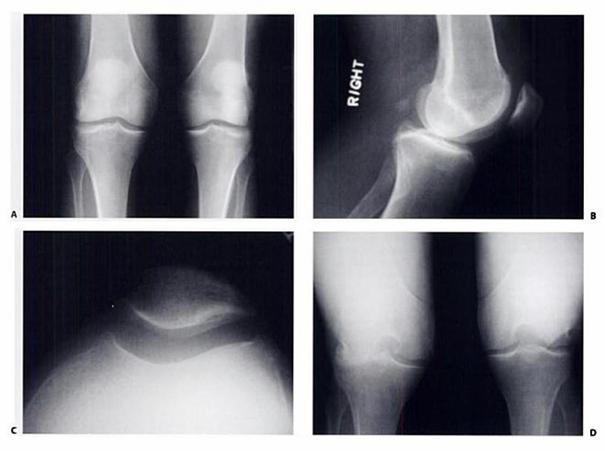

Fig.15. A- radiografie antero-posterioara ; B- radiografie laterala; C- vedere axiala a patelei; D- radiografie